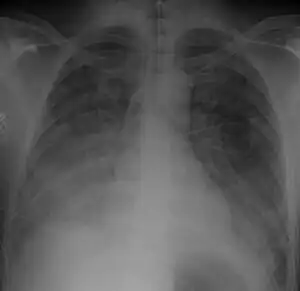

| Chest X-ray of a 40 yr old with acute respiratory distress syndrome as a complication of murine typhus | |